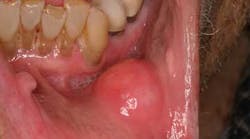

The lips: The lips should be evaluated with the mouth open and closed, noting any abnormalities in symmetry, contour, color, or texture. Attention to the vermilion border of the lower lip is warranted as this is a prime site for oral cancers. First, revert the lower lip and inspect the inner surface. The labial mucosa should be smooth and uniform in color. Notice the frenum of the lip in the midline. Note any signs of smokeless tobacco use (ulcers, red or white discolorations, texture variations) on the labial mucosa. With the lip still retracted, one can also inspect the gingivolabial sulcus, the gingival mucosa, and the teeth. Next, palpate the lip with your thumb and index finger, noting any firm or nodular submucosal areas (figure 1). Repeat these steps for the upper lip.